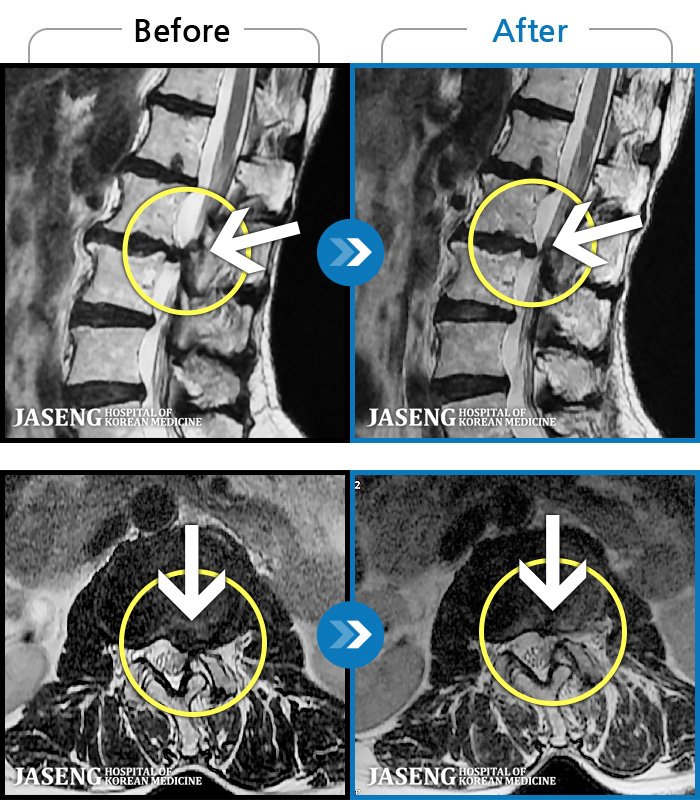

허리디스크

해운대 · 김상돈 원장

허리 골반 통증이 있고 허리를 숙일 때 불편합니다.

촬영시기

2020.09.14 ~ 2025.07.09

2025.07.11